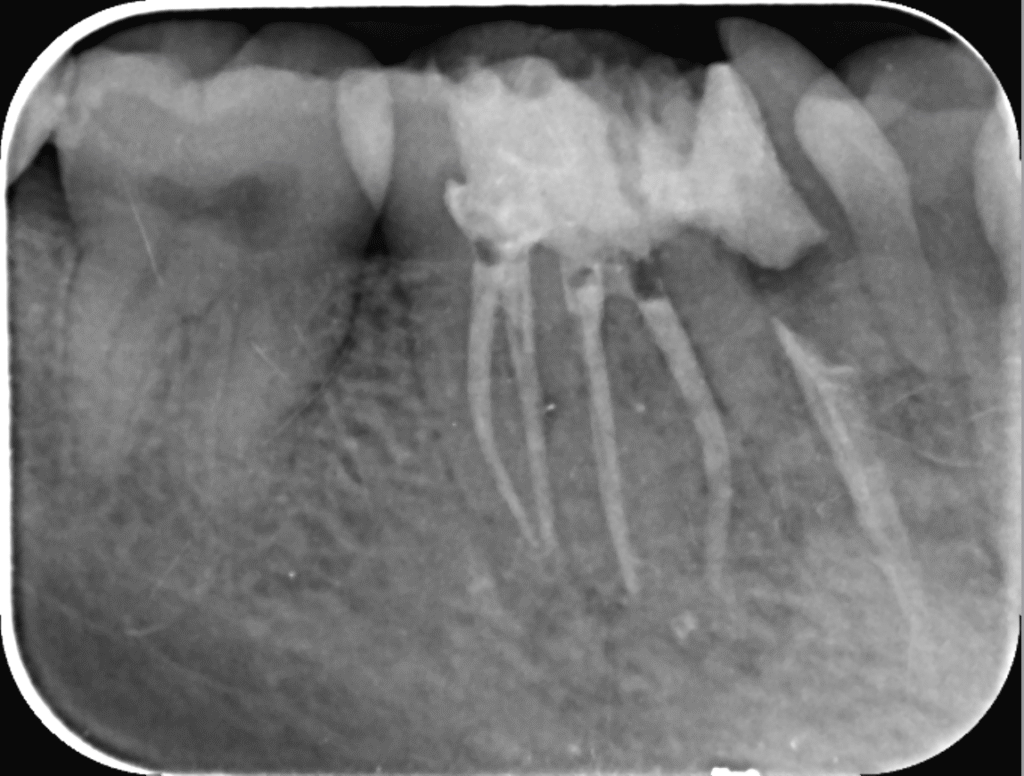

در ابتدا، دندانپزشک یک معاینه کامل انجام می‌دهد و با استفاده از تصاویر اشعه ایکس، وضعیت دندان را بررسی می‌کند. این مرحله برای تعیین نیاز به درمان مجدد و برنامه‌ریزی مراحل بعدی حیاتی است. در این جلسه، دندانپزشک ممکن است سوالاتی درباره تاریخچه پزشکی و دندانی بیمار بپرسد.

بررسی مجدد وضعیت دندان

پس از پاکسازی، دندانپزشک دوباره وضعیت دندان را بررسی می‌کند تا اطمینان حاصل کند که تمام عفونت‌ها و باکتری‌ها از بین رفته‌اند. در این مرحله ممکن است دوباره تصاویر اشعه ایکس گرفته شود.